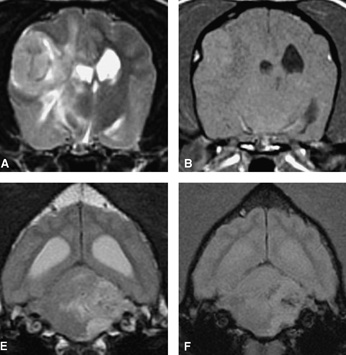

La risonanza magnetica risulta insostituibile come esame nelle lesioni cerebrali in particolare per lo studio dell'epilessia primaria o idiopatica, nello studio come le malformazioni congeniti quali l'idrocefalo nel cucciolo in età di sviluppo, nel tumore primario celebrale (meningiomi, gliomi, blastomi) o nelle metastasi cerebrali, nella malformazione come la sindrome di Chiari (particolarmente colpita la razza del Kink Cavalier). Nelle emoragie craniche post-traumatiche, nello studio dell'adenoma della ghiandola ipofisaria, nello studio dell'area retrobulbare oculare.